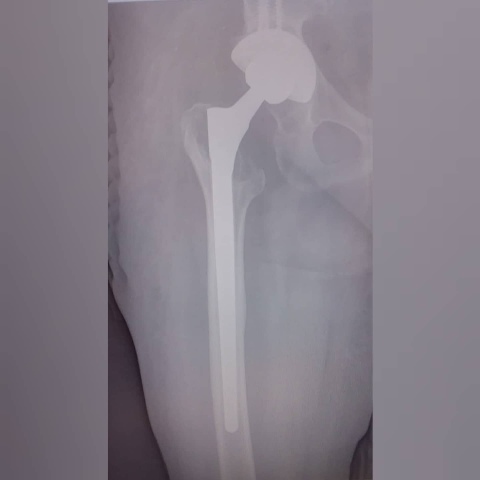

Речь идёт о полной или частичной замене ранее установленного эндопротеза. В данном виде операции нуждаются пациенты, которым ранее установили искусственный сустав, но по какой-то причине возникли осложнения, либо потребовалась его замена. По статистике таких пациентов немного — всего 1-2%, но в каждом случае требуется высокотехнологичная медицинская помощь.

Реэндопротезирование проводится в клиниках экспертного уровня. Раньше многих пациентов из Красноярского края на данную операцию направляли в федеральные центры других регионов. Теперь же это можно делать и у нас. Что немаловажно, это позволит сократить сроки дооперационного периода.

Для проведения таких операций в больнице имеется необходимое оборудование, в том числе и расходные материалы. Доктора БСМП прошли обучение и сотрудничают с коллегами из Новосибирского НИИТО, НМИЦ ТО им. Р.Р. Вредена Санкт-Петербурга и других клиник.